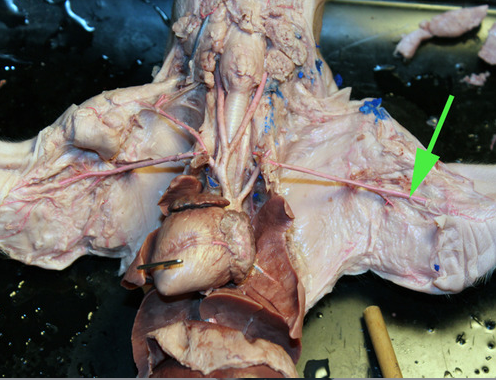

The brachiocephalic artery is marked by the green arrow

The artery marked by the green arrow is the left subclavian artery

The artery marked by the green arrow is the common carotid artery.

The artery marked by the green arrow is the AORTA artery.